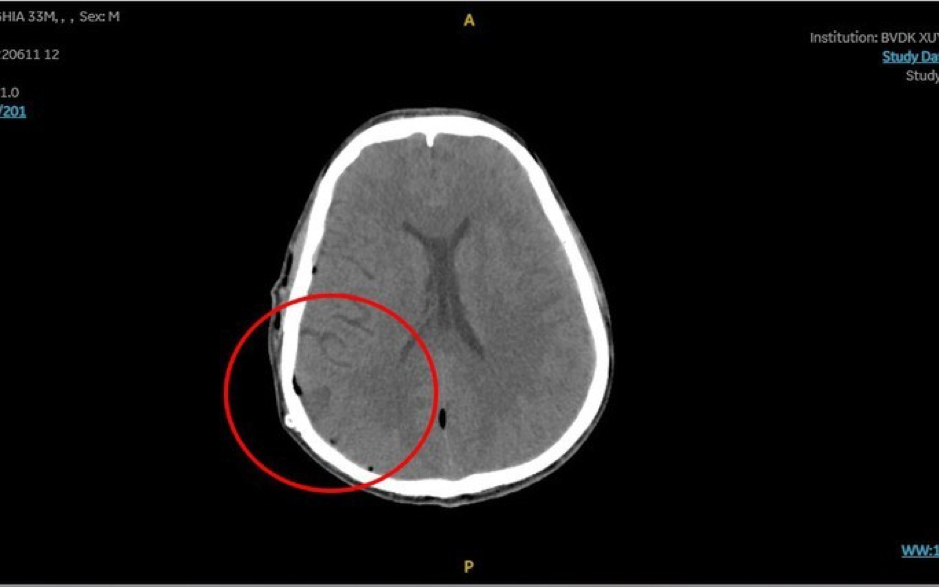

Khối máu tụ khi vào viện gây chèn ép não. Ảnh: BVCC

Khối máu tụ khi vào viện gây chèn ép não. Ảnh: BVCC

Ê kíp đã nhanh chóng đặt nội khí quản kiểm soát đường thở cho anh N. Theo đó, chụp MSCT Scan sọ não ghi nhận khối máu tụ ngoài màng cứng đính phải, lượng rất nhiều, chèn ép nhu mô não, gây thoát vị não một trong những dấu hiệu nặng gây nguy kịch tính mạng bệnh nhân.